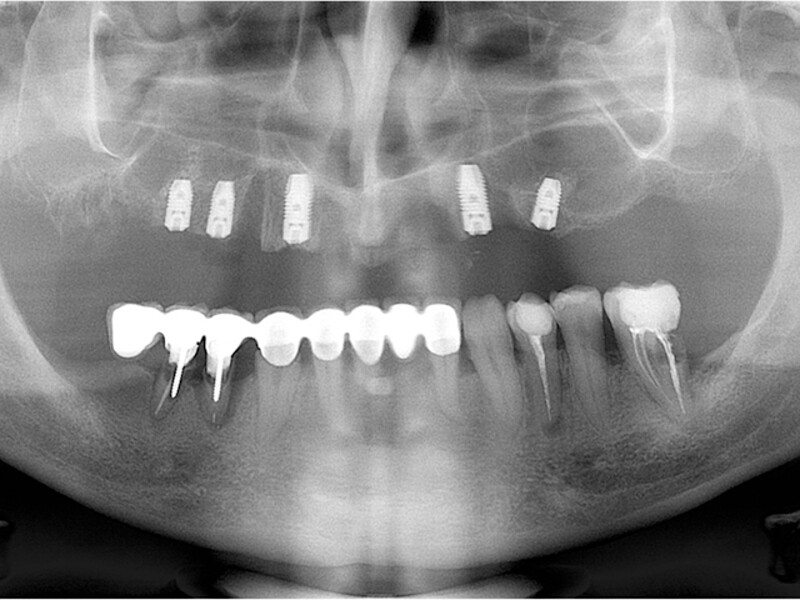

MAGICAL All on FOUR